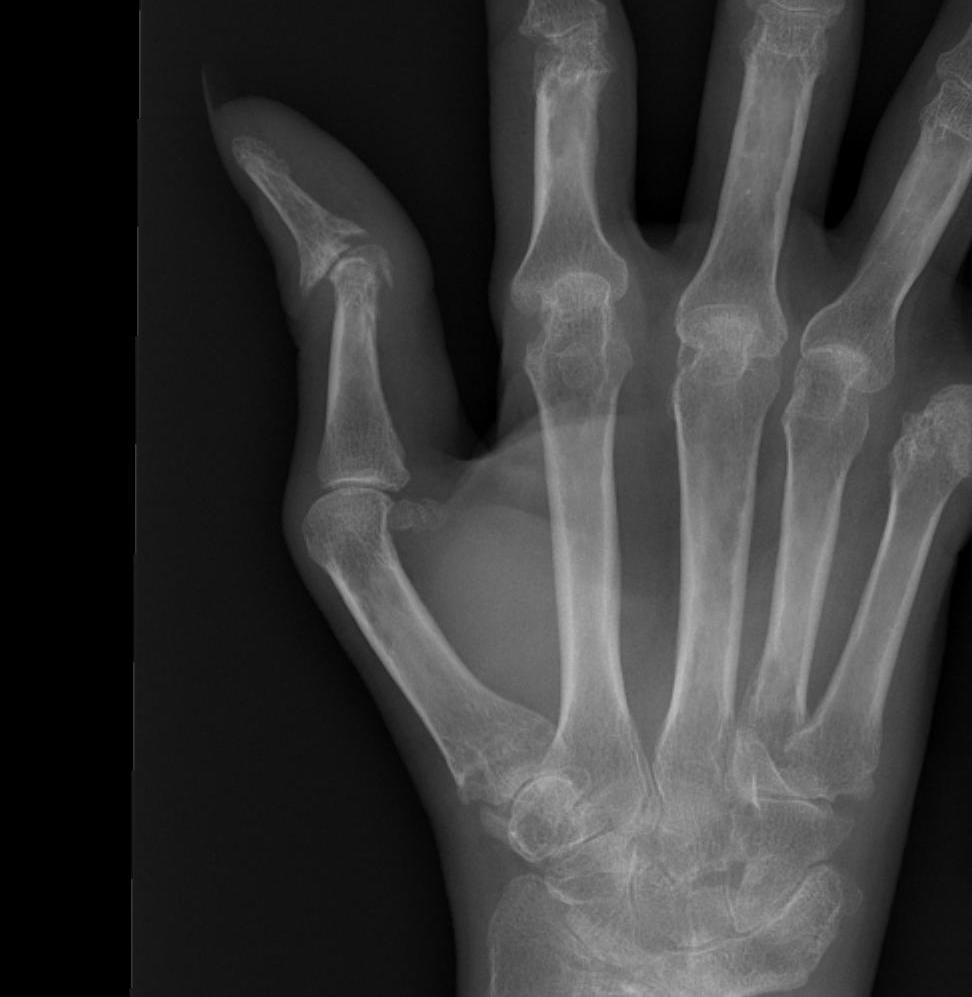

Type III - Swan Neck

- second most common

- primary deformity is OA and dorsal subluxation of CMC

- hyperextension MPJ / IPJ flex